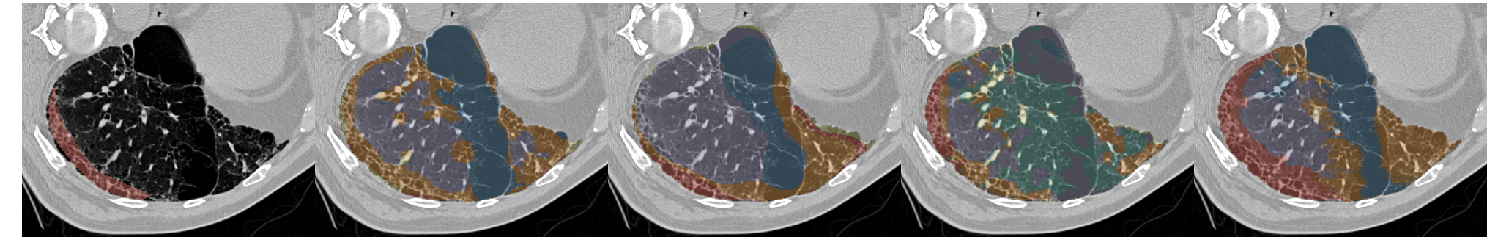

Table III presents a comparison between the proposed network and three previous studies. It has to be noted that all models used the same unsupervised weight (wu=0.1subscript𝑤𝑢0.1w_{u}=0.1) and whenever batch normalization was performed, this was based on batch statistics (instance normalization) since this yielded the best results. Fig. 7 illustrates a few segmentation results for each of the models in Table III.

The first line of the table refers to our previous work [5], which has been converted into a fully convolutional network so it can accept arbitrarily sized images for input. Its low accuracy is probably due to the small receptive field (33×\times33) and the extensive pooling. This architecture was sufficient to describe the local texture of the 32×\times32 single-class patches in [5], but could not capture higher level structure that is present in the whole-lung dataset of this study. The results of the model in Fig. 7 show its noisy output near the lung boundaries or between patterns, where context information could be useful. Segnet [15] and U-net [17] yielded better results, with the latter being slightly faster and substantially more accurate. Both models have a very high number of parameters and large enough receptive fields to capture any relevant information. The superior performance of U-net could be attributed to its skip connections that allow features from the lower scales to directly contribute to its output. Indeed, Fig. 7 illustrates the more detailed results of U-net as opposed to the overly smoothed areas produced by Segnet. Finally, the proposed network yielded the best results, while being faster and having far fewer parameters. The output examples in Fig. 7 indicate that the proposed model manages to keep a better balance between fine details and smooth border among the different classes. Even thought it is really difficult to visually assess the performance of the system for the different classes, there are a few examples in Fig. 7 with wrong classifications on which we can comment. Firstly, parts of the broncho-vascular tree in the third row were recognized as consolidation because of their similar densities, while accentuated terminal bronchial parts, that might be physiological as well, caused the erroneous classification of healthy areas into reticulation, in the first row. Some mistakes however are also attributed in the limited number of annotated classes. For example in row 6, there are emphysematic areas (dark area in the center of the lung) that have been annotated as healthy due to their similar density. Figure 6 shows the confusion matrix of the proposed model. As expected, many of the misclassifications occur between reticulation and honeycombing due to their similar textural appearance. Moreover, healthy tissue is often confused with reticulation probably because of the 2D sections of the bronchovascular tree that could resemble reticular patterns.

Refer to caption

Figure 7: Output examples for the models of Table III. From left to right: Ground Truth, ILD-CNN, Segnet, U-net, Proposed. Each example has a different pattern annotated. From top to bottom: Healthy (Blue), Ground Glass Opacity (Purple), Micronodules (Green), Consolidation (Yellow), Reticulation (Orange) and Honeycombing (Red).